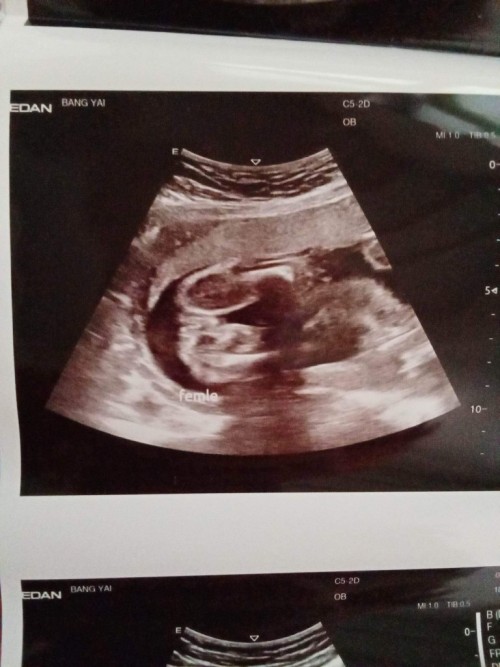

แม่ๆช่วยดูหน่อยค่ะ

แบบนี้ผู้หญิงหรือว่าผู้ชายหรอคะ

ของคุณแม่ได้ผู้หญิงคะ ถ้าได้ผู้ชายจู๋น้องจะโพล่ออกมาแบบนี้เหมือนของเราค่ะ เราได้ลูกชาย

จากประสบการณ์มีลูกทั้งชายและหญิง คิดว่าผญ.ค่ะ ถ้าผช.จะมีจุดจู๋ชี้ขึ้นมาเลยค่ะ

ลูกสาวค่ะคุณแม่ เหมือนของเรา ถ้าชายจะโด่ออกมาเลย จากประสบการณ์มีลูกชายมา 2 คน 🥰

แบบนี้ผู้หญิงค่ะ บ้านนี้ก็ได้ภาพแบบนี้เหมือนกัน

แฮมเบอร์เกอร์แบบนี้น่าจะเป็นผญค่ะ ถ้าผชน่าจะเห็นงวงแล้วว

ซาวด์ได้แบบนี้เหมือนกันค่ะ หมอบอกน่าจะผู้หญิงค่ะ